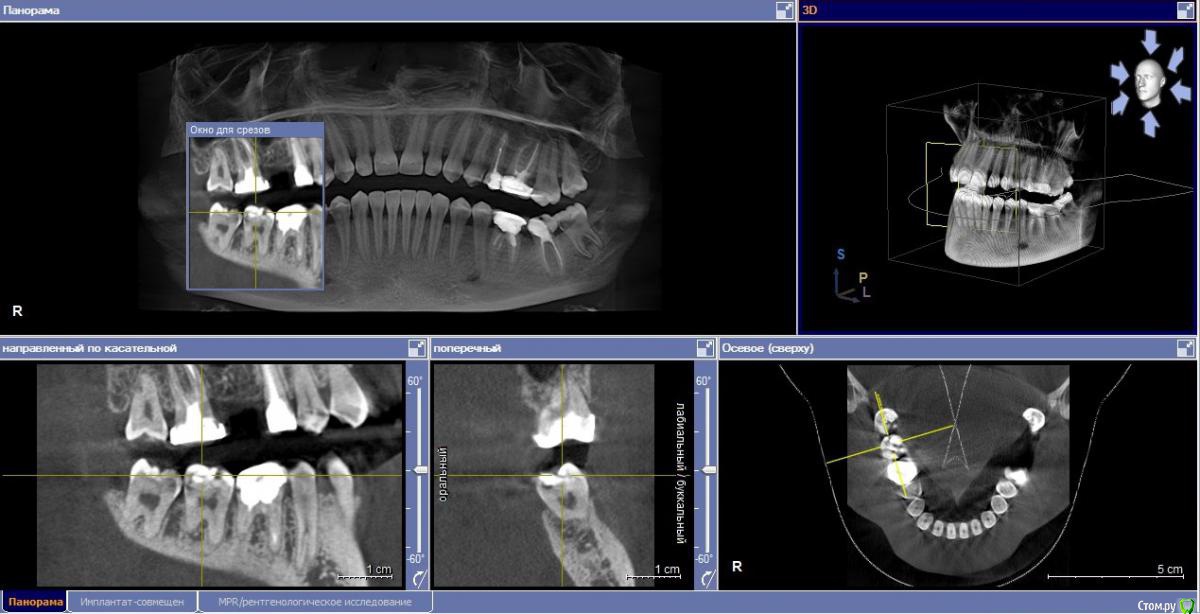

Софья Djcnhbrjdf Опубликовано 21 декабря, 2016 Поделиться Опубликовано 21 декабря, 2016 (изменено) Здравствуйте! Совсем не знаю как быть. На НЧ требуется удалить справа 6ку, т.к там большая киста. В то же время на левой стороне есть проблемный зуб (7), от него только половина, предложили сделать вкладку и коронку,но при более тщательном осмотре врач сказал, что ставить вкладку рискованно - очень большой дефект. Может быть воспаление и долгое время не простоит. Склоняюсь к варианту удалить этот зуб. Но и с зубом с кистой не хочу затягивать. Удалить два сразу? Или по очереди? На сколько опасно тянуть?А что после удаления? Мост врач сказал не поставит на 8ку. Справа живые зубы обтачивать не хочется. Можно ли с помощью системы брекетов перетянуть зубы? Прочитала в интернете, что такой вариант возможен. На место 7ки слева 8ку, а справа на место 6ки 7ку и 8ку? Или имплантация?( Деньги тоже играют роль)У врача, правда, еще не консультировалась. Спрашиваю потому что заинтересовалась вариантом брекетов. Прикрепляю скрин моего КТ. На данный момент справа сверху мост, 8ка слева вылечена, оставили живой. Изменено 21 декабря, 2016 пользователем Софья Djcnhbrjdf Ссылка на комментарий

Жандос Муратович Опубликовано 21 декабря, 2016 Поделиться Опубликовано 21 декабря, 2016 Здравствуйте! Совсем не знаю как быть. На НЧ требуется удалить справа 6ку, т.к там большая киста. В то же время на левой стороне есть проблемный зуб (7), от него только половина, предложили сделать вкладку и коронку,но при более тщательном осмотре врач сказал, что ставить вкладку рискованно - очень большой дефект. Может быть воспаление и долгое время не простоит. Склоняюсь к варианту удалить этот зуб. Но и с зубом с кистой не хочу затягивать. Удалить два сразу? Или по очереди? На сколько опасно тянуть? А что после удаления? Мост врач сказал не поставит на 8ку. Справа живые зубы обтачивать не хочется. Можно ли с помощью системы брекетов перетянуть зубы? Прочитала в интернете, что такой вариант возможен. На место 7ки слева 8ку, а справа на место 6ки 7ку и 8ку? Или имплантация?( Деньги тоже играют роль) У врача, правда, еще не консультировалась. Спрашиваю потому что заинтересовалась вариантом брекетов. Прикрепляю скрин моего КТ. На данный момент справа сверху мост, 8ка слева вылечена, оставили живой. Дешевле имплант поставить,7 и 8 можно передвинуть, но там нужны будет ставить микроимпланты и все такое(дорого) Ссылка на комментарий